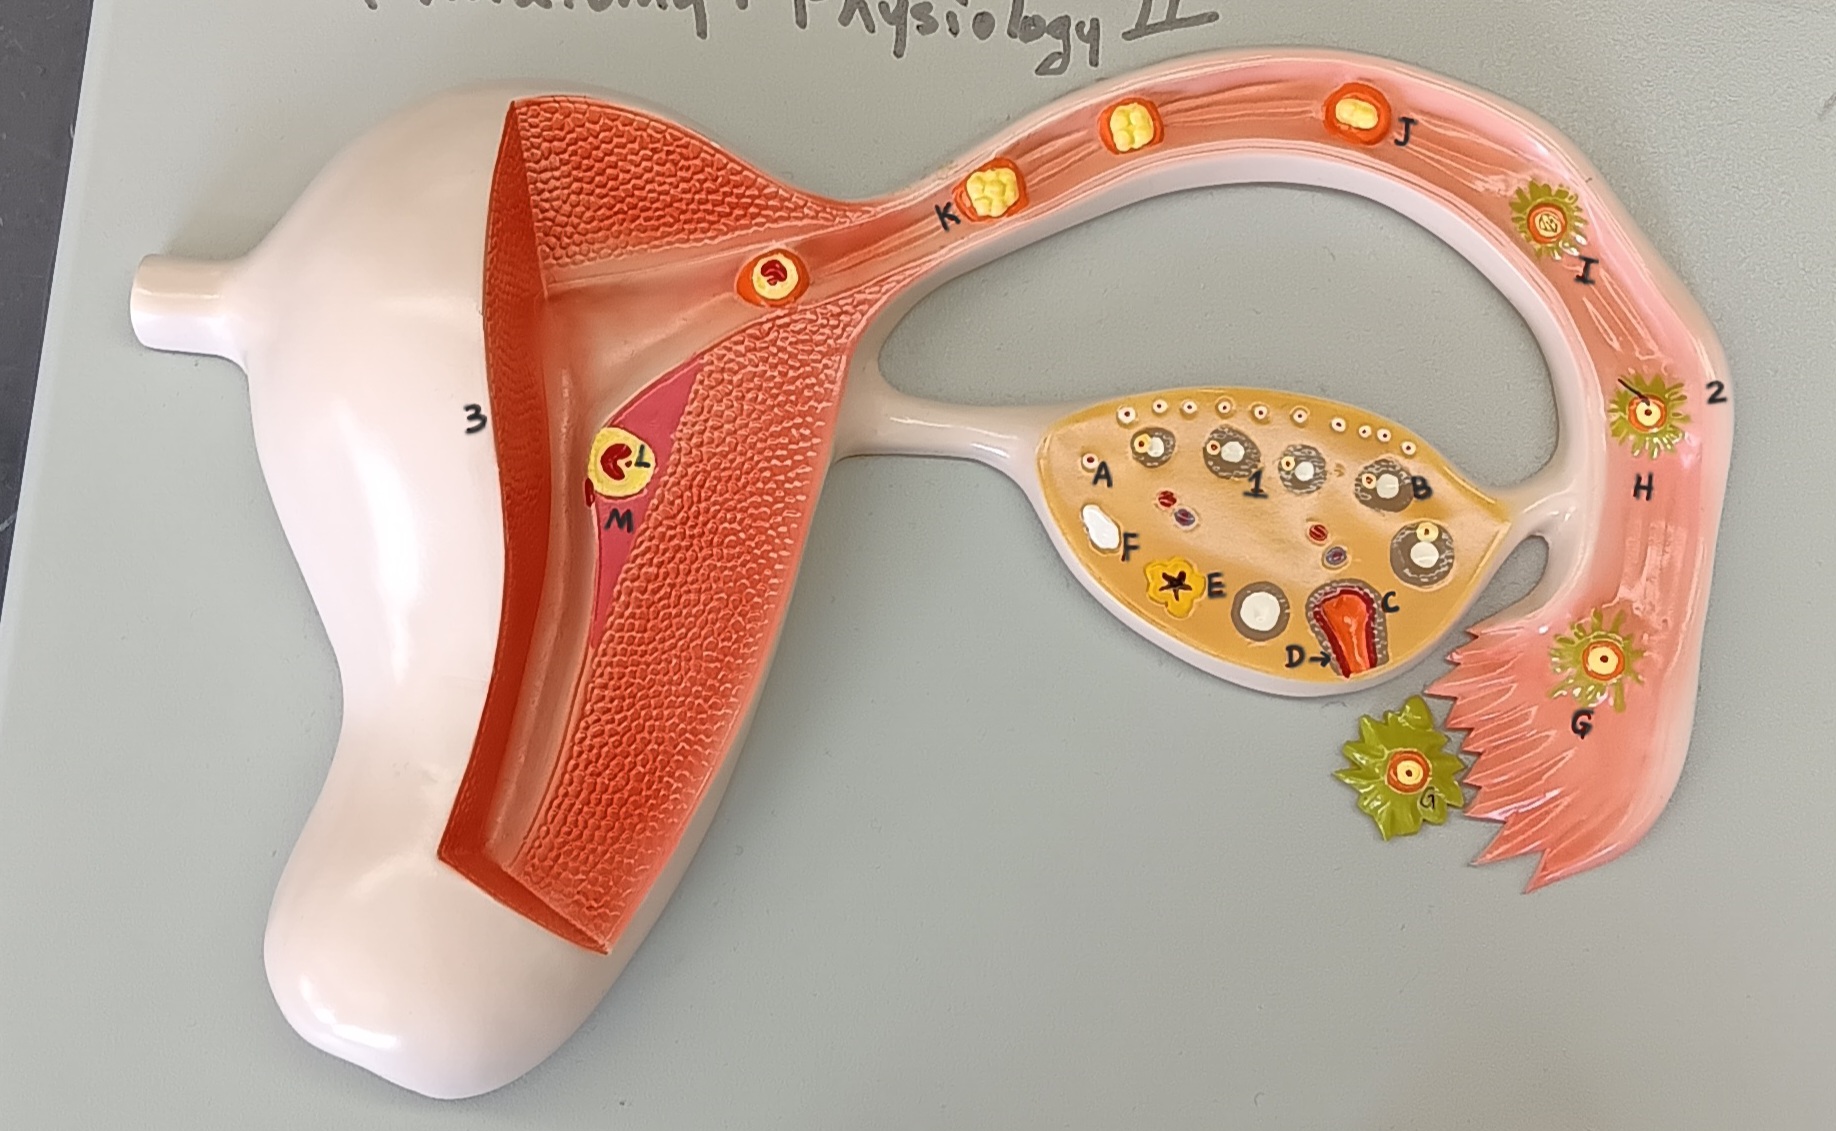

ovary

1

primordial follicle

a

secondary follicle

b

ruptured follicle

c

granulosa cells

d

corpus luteum

e

secondary oocyte

g

ovum

h

zygote

i

blastocyst

l

endometrium

m

corpus albicans

f

uterus

3

fallopian tube

2